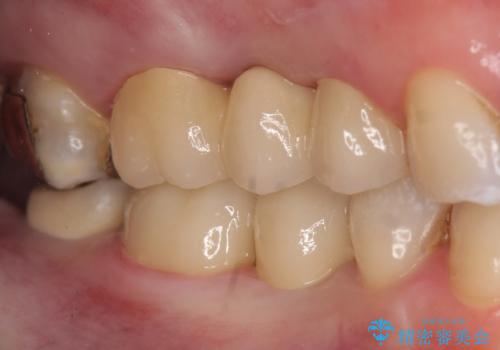

オールセラミッククラウンについて

今回用いたオールセラミッククラウンはジルコニアフレームという白い素材の上にセラミックを盛っているため、審美性が非常に高いのが特徴です。

また、ジルコニアは人工ダイヤモンドの材料にも使われているほど高い強度を持っており、そのためオールセラミッククラウンは審美性だけでなく、奥歯やブリッジの補綴も可能とするクラウンです。